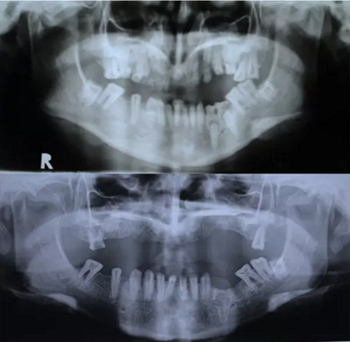

該患者 12 歲時(shí)已診斷為釉質(zhì)發(fā)育不全。家族史正常,否認(rèn)全身系統(tǒng)性疾病。全身系統(tǒng)檢查無明顯異常,檢查雙側(cè)顳下頜關(guān)節(jié)、開口度正常??趦?nèi)及 X 片檢查見上頜縮窄,上頜牙列缺失,安氏三類錯(cuò)牙合,下頜牙牙冠短小,牙根正常。上頜大量牙槽骨因以前手術(shù)干預(yù)而喪失,后牙區(qū)牙槽骨高于前牙區(qū)。病變牙齒在之前的治療中已被拔除。

圖 2. 曲面斷層片(術(shù)前、拔牙后、種牙后)